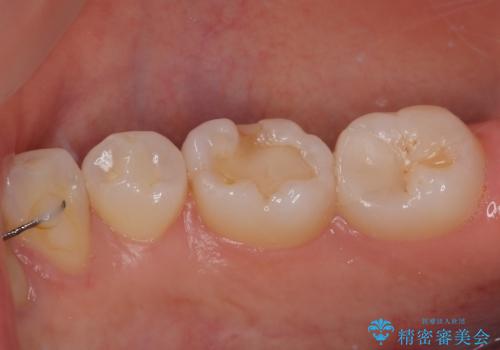

歯と歯茎の間に圧排糸と言われる糸を入れてシリコーン印象材にて精密な型どりをしました。

セラミックインレーの装着時には、唾液の侵入を防ぐために、ラバーダム防湿を行いました。